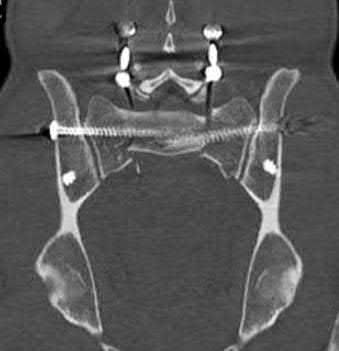

Question 1:

During an anterior intrapelvic (modified Stoppa) approach for the fixation of an acetabular fracture, the surgeon encounters significant bleeding from a vascular anastomosis situated over the superior pubic ramus. What two main vessels typically form this specific anastomosis (Corona Mortis)?

Correct Answer: Inferior epigastric artery and obturator artery

Explanation:

The corona mortis ('crown of death') is a vascular anastomosis between the external iliac and internal iliac vascular systems. Specifically, it connects the inferior epigastric artery or vein (from the external iliac system) to the obturator artery or vein (from the internal iliac system). It is located on the posterior aspect of the superior pubic ramus, approximately 4-7 cm from the pubic symphysis, and is at high risk of iatrogenic injury during the modified Stoppa or ilioinguinal approaches.